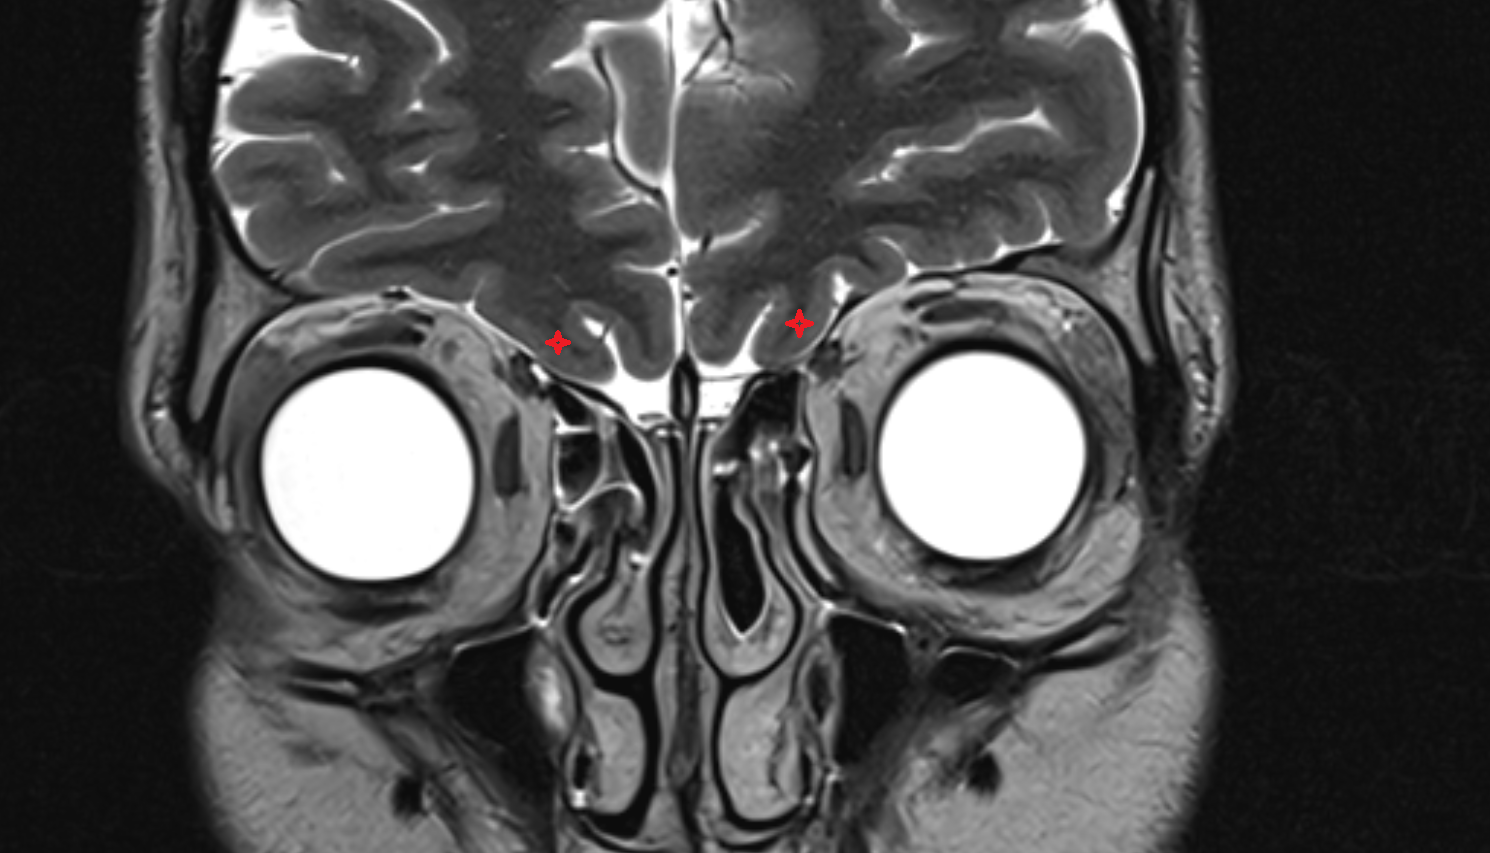

- Optic chiasm